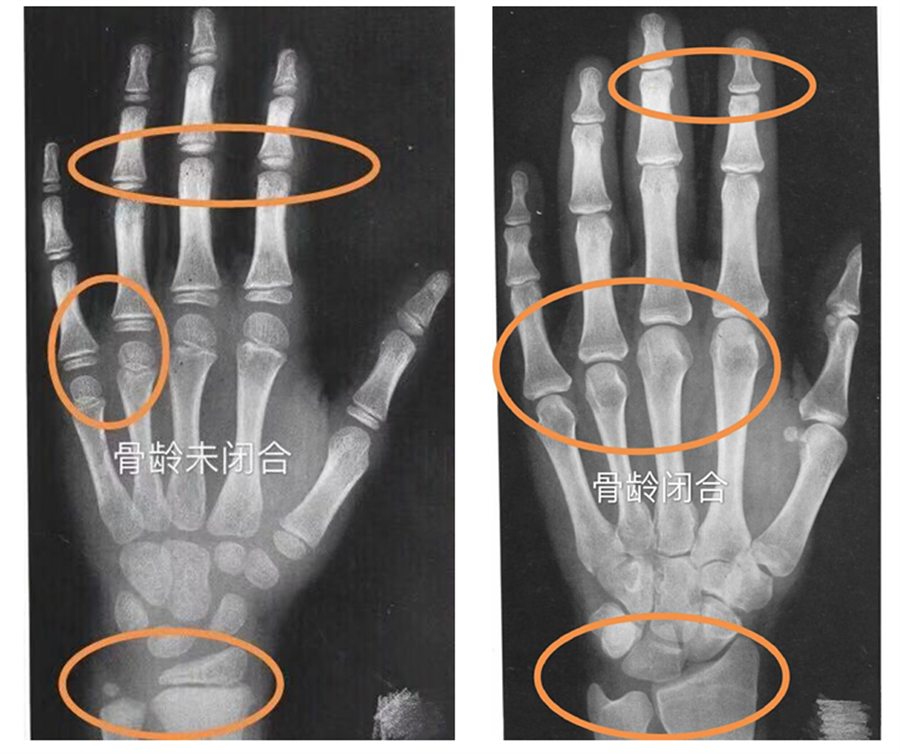

而骨龄是以骨骼发育(钙化)程度和标准骨龄进行比较所求得的一种发育年龄,是反映个体发育水平和成熟程度比较精确的指标,骨龄评估能较准确地反映个体的生长发育水平和成熟程度,对于儿童的生长发育管理有很大的指导意义。